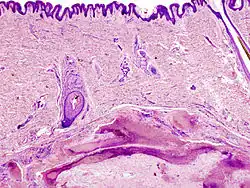

Pilomatrixome

Le pilomatrixome (ou "pilomatricome", ou "épithéliome calcifié de Malherbe") est une tumeur bénigne cutanée d'origine annexielle folliculaire. La tumeur survient surtout chez les enfants et les adolescents avec prédominence féminine et se localise au niveau de la tête et du cou[1]. Cliniquement on trouvera fréquemment un nodule sous-cutané unique, de taille inférieure à 3 cm et asymptomatique (parfois douloureux)[2].